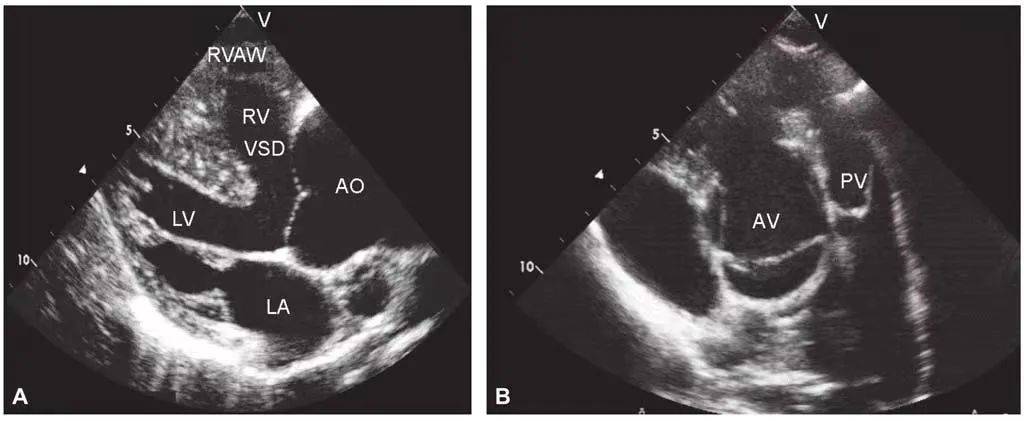

是联合的先天性心脏血管畸形,包括肺动脉口狭窄,心室间隔缺损,主动脉